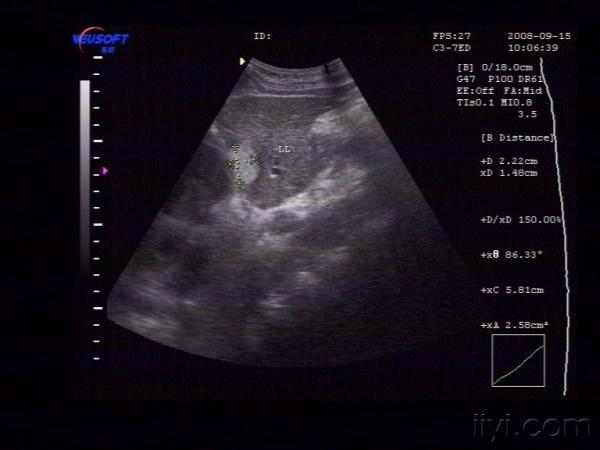

【贴图】肝脏血管瘤

体检发现左肝内一较强回声团,大小约为29X22X15mm,边界清,中央回声稍低。CDFI:未见异常血流信号